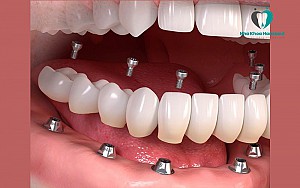

2.4 Implant All On 6

Implant All On 6 là giải pháp cải tiến hơn all on 4 khi sử dụng 6 trụ Implant để đặt vào xương hàm bệnh nhân. Với kỹ thuật All On 6, các trụ chân răng thường được dựng thẳng đứng. Vị trí lắp đặt cũng được phân bố đều khắp cả hàm.

Kỹ thuật này được sử dụng khi xương hàm của bệnh nhân mỏng hơn hoặc không đủ chắc chắn để sử dụng phương pháp implant all on 4.